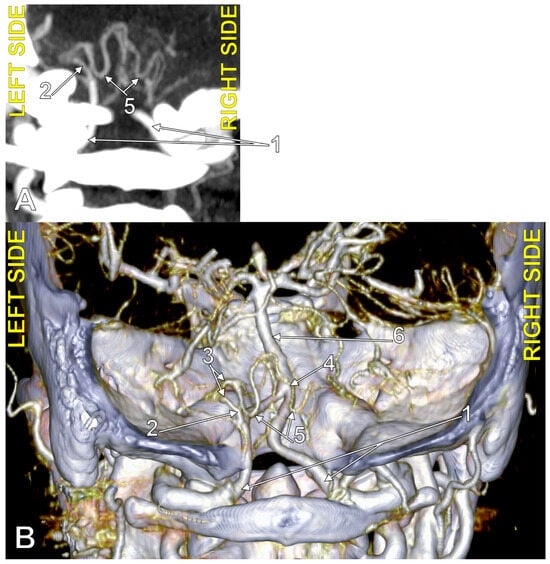

4.3. Extradural Origin of the PICA

4.4. Transdural Origin of the PICA